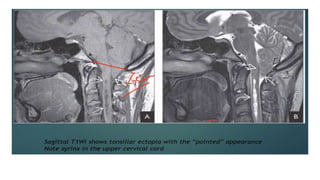

Imaging Chiari I Malformations

• The imaging method of choice is MRI

• The tonsillar herniation was noted to be clearly patho- logic when it

exceeded 5 mm and borderline between 3 and 5 mm.

Cerebrospinal Fluid Flow Studies and Cine-

ModeMagnetic Resonance Imaging

• One technique to assist in the surgical decision making of

patients with Chiari malformations is motion-sensitive MRI, or

cine- mode MRI.

• As opposed to static MRI, cine MRI may demonstrate lack of CSF

flow patterns that can occur in the setting of CIM.